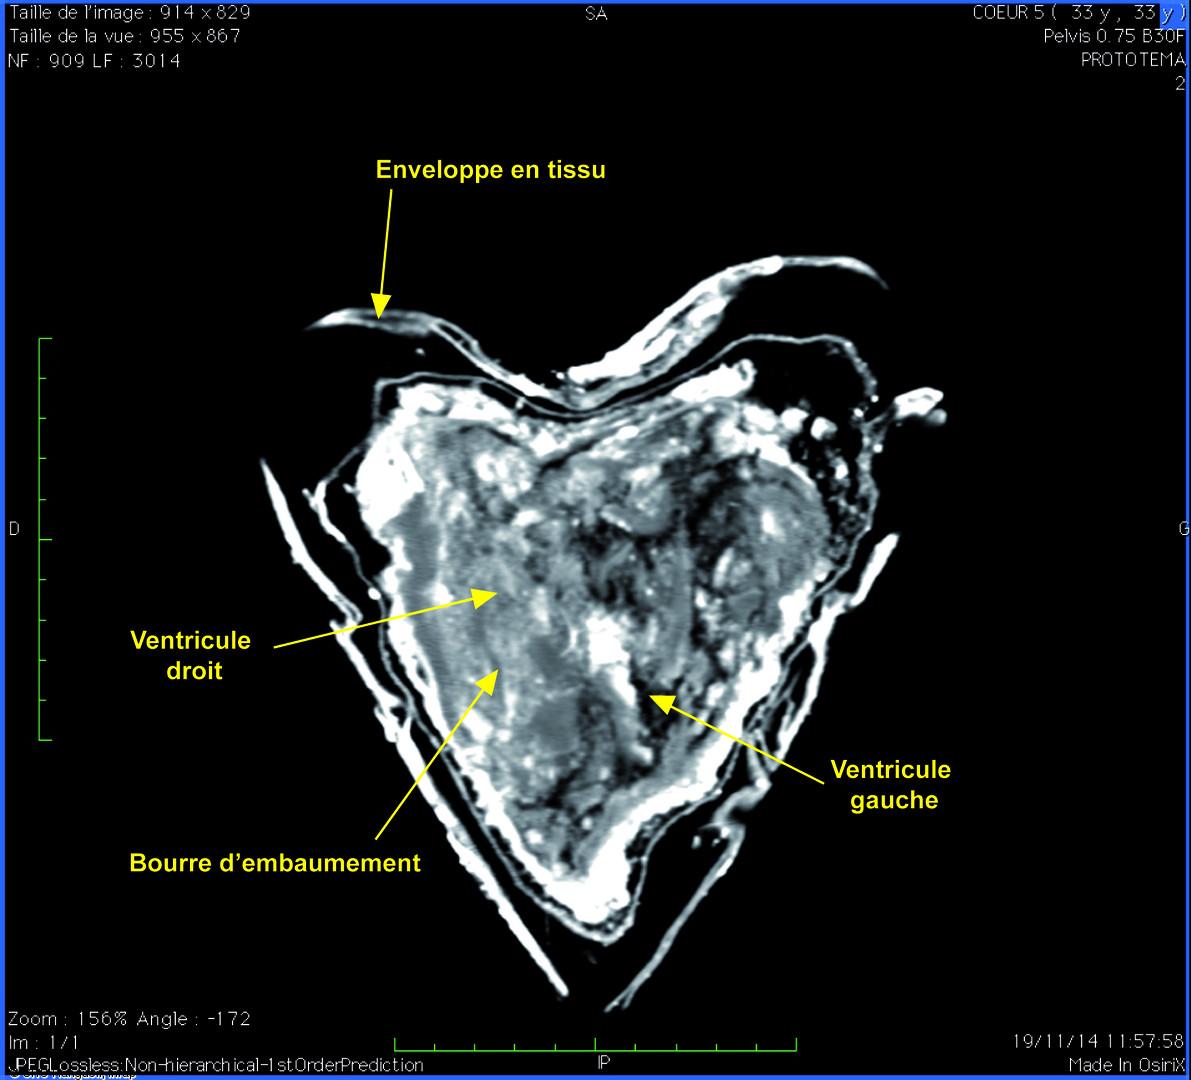

Một bức chụp cắt lớp thi hài của Louise De Quengo cho thấy trái tim ở trạng thái bảo quản tốt nhờ quan tài được hàn chặt kín.